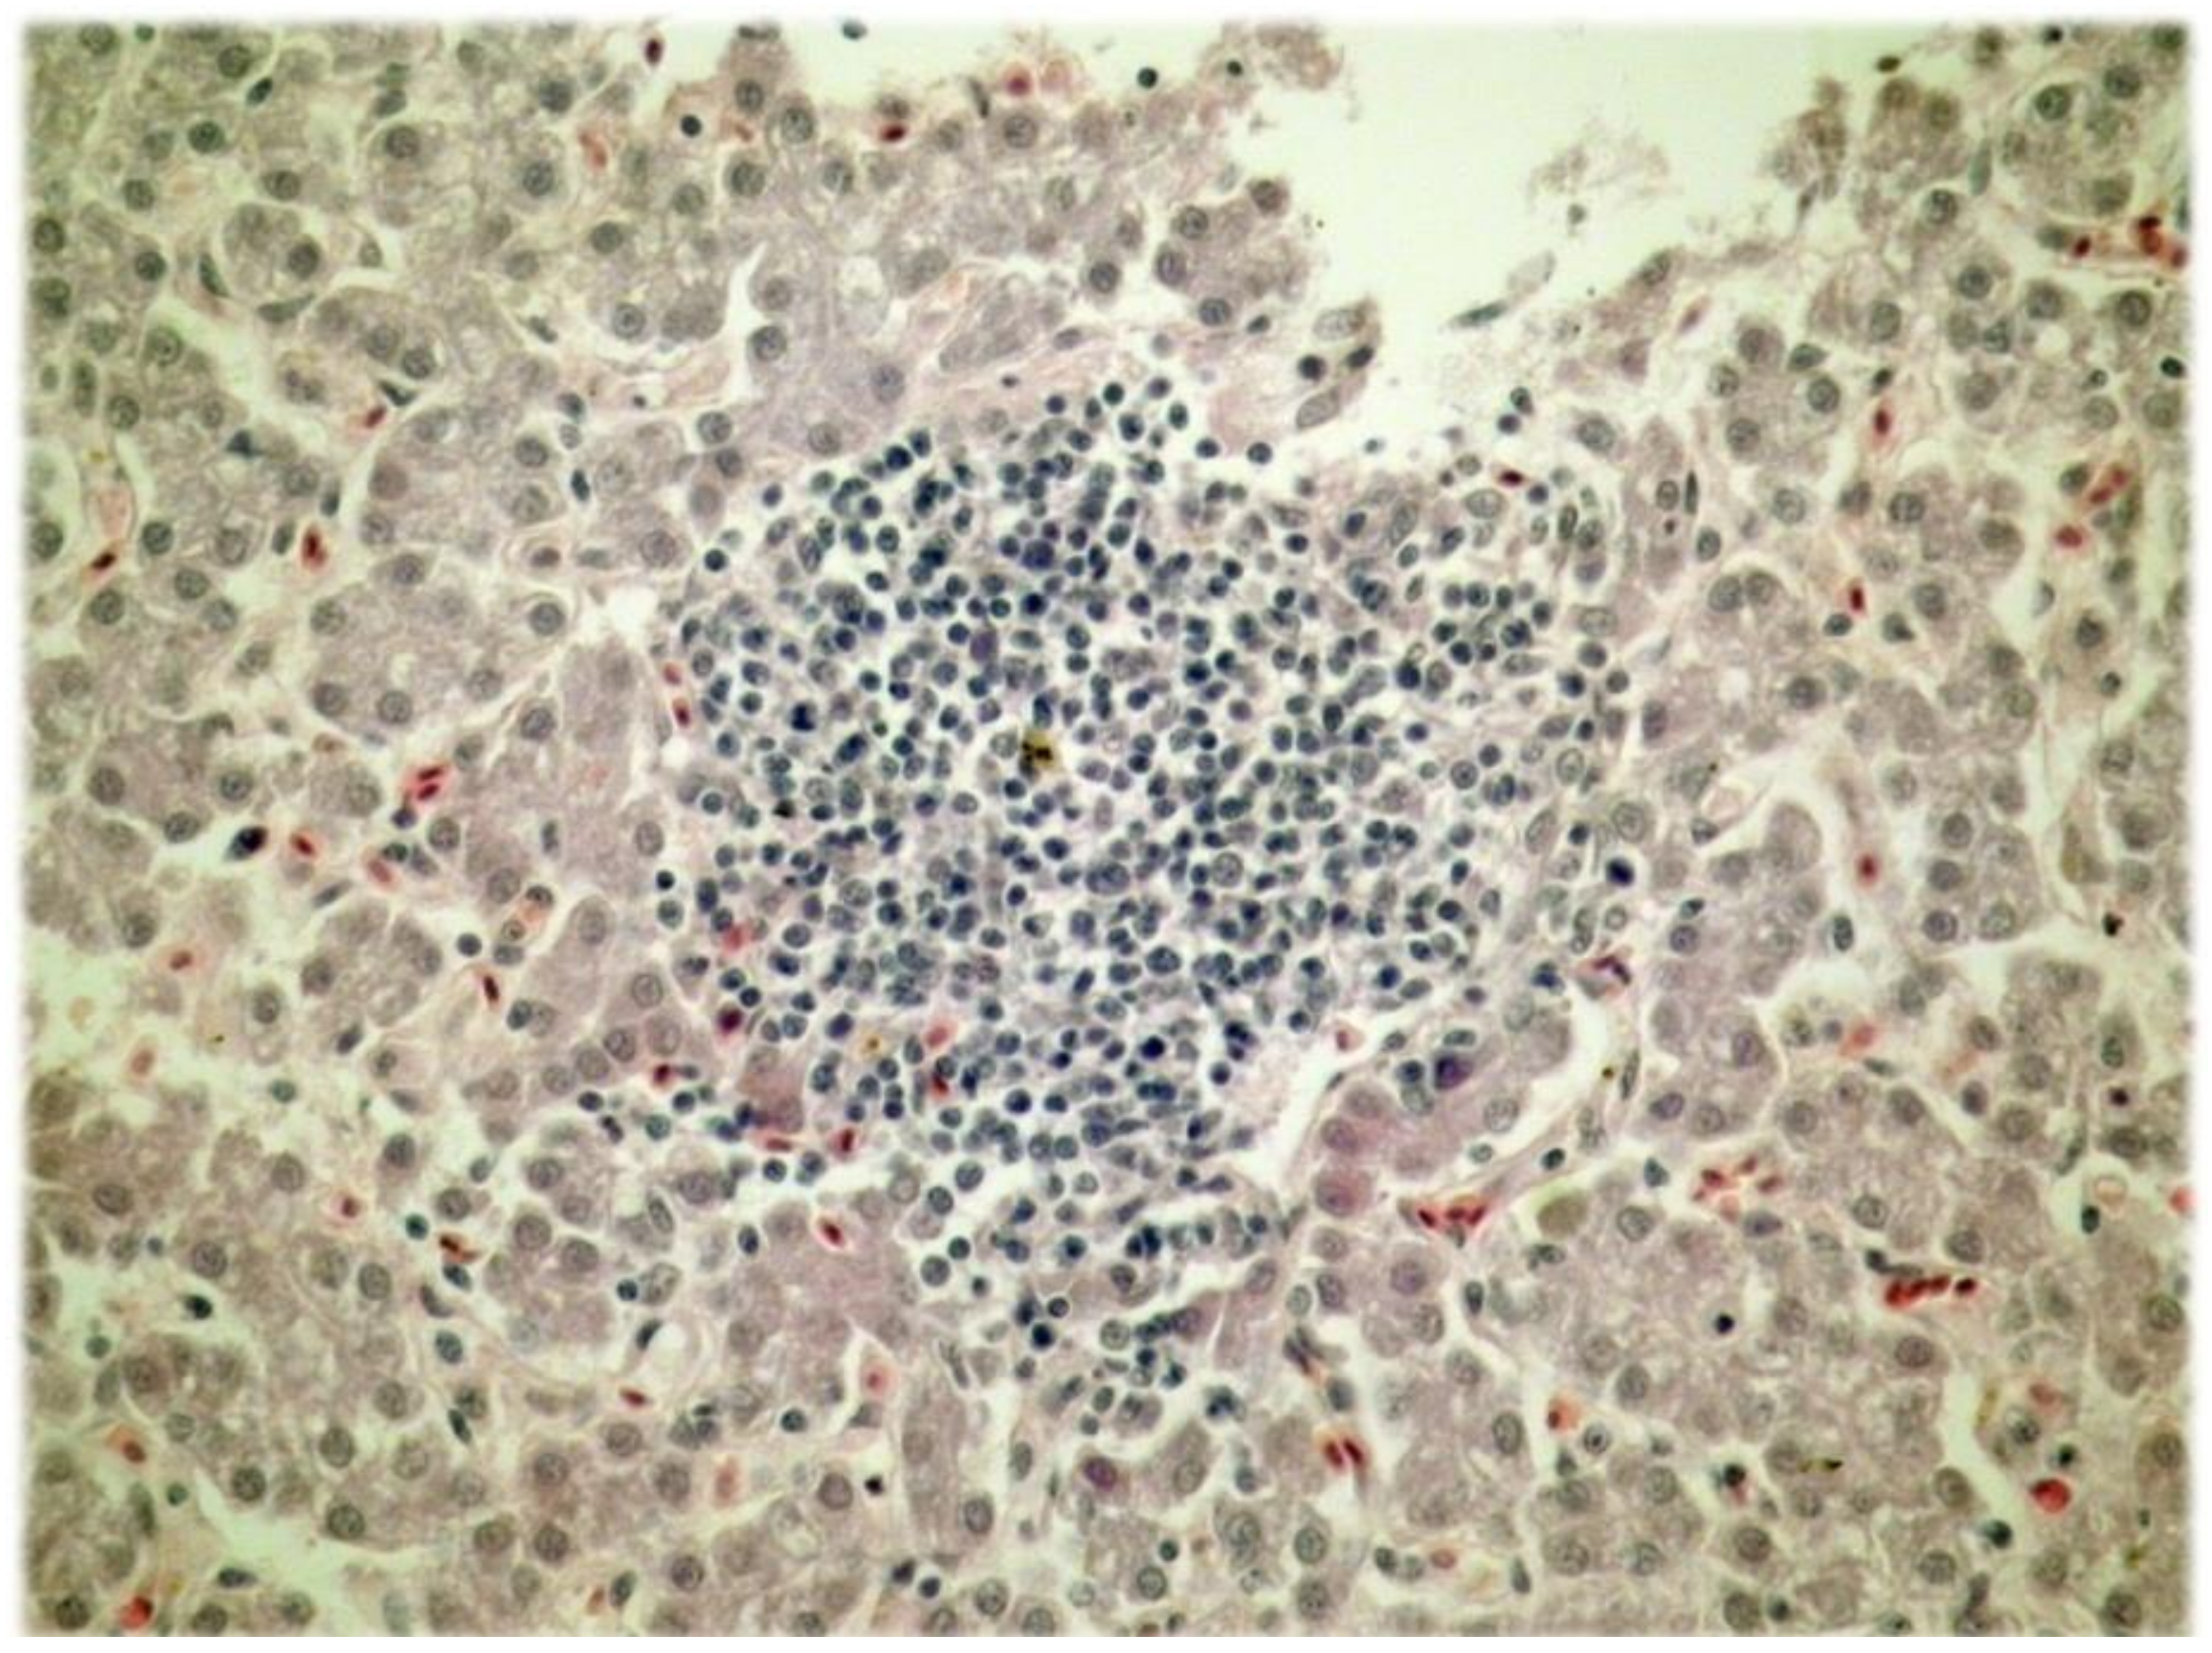

| The forms of regressive lesions of hepatocytes | Group of chickens | * p | |||||

|---|---|---|---|---|---|---|---|

| Control (K) | P1 | P2 | P3 | P4 | |||

| Degeneration of the liver parenchyma | Yes % | 90.0 | 60.0 | 70.0 | 60.0 | 60.0 | 0.507 |

| No % | 10.0 | 40.0 | 30.0 | 40.0 | 40.0 | ||

| Vacuolar degeneration of the liver parenchyma | Yes % | 90.0 | 10.0 | 20.0 | 0 | 0 | <0.001 |

| No % | 10.0 | 90.0 | 80.0 | 100.0 | 100.0 | ||

| Steatosis of the liver parenchyma | Yes % | 90.0 | 90.0 | 60.0 | 60.0 | 70.0 | 0.319 |

| No % | 10.0 | 10.0 | 40.0 | 40.0 | 30.0 | ||

| Necrosis of the liver parenchyma | Yes % | 100.0 | 30.0 | 0 | 0 | 10.0 | <0.001 |

| No % | 0 | 70.0 | 100.0 | 100.0 | 90.0 | ||

| The forms of pathological changes in the liver veins | Group of chicken | * p | |||||

| Thickening of the walls of veins | Yes % | 100.0 | 10.0 | 10.0 | 10.0 | 10.0 | <0.001 |

| No % | 0 | 90.0 | 90.0 | 90.0 | 90.0 | ||

| The hyperplasia of the fibrous tissue within the walls of the veins | Yes % | 100.0 | 10.0 | 10.0 | 10.0 | 10.0 | <0.001 |